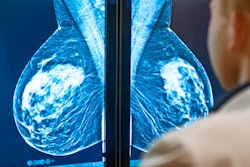

Researchers led by Dr. Yunan Han from the Washington University School of Medicine in St. Louis found that volumetric percent density and the odds of having dense breasts were significantly higher in women with family history compared to those without family history.

"The findings highlight the heritable component of mammographic breast density and underscore the need to begin annual screening early in premenopausal women with a family history of breast cancer," Han's team wrote.

The study authors found that women in the discovery set who had a family history of breast cancer were more likely to have a higher average volumetric percent density at 11.1% than those without family history at 9%.

Volumetric percent density was 25% higher with an odds ratio of 1.25 in women with a family history of breast cancer when multiple variables were accounted for. It was also 24% higher with an odds ratio of 1.24 in women who had one affected relative. However, density was not significantly higher in women who had at least two affected relatives (odds ratio) compared with women with no relatives affected.

The researchers found similar trends in the validation set. Here, women with a positive family history of breast cancer were more likely to have dense breasts at 41.1% for BI-RADS 3 compared with those with no family history at 38.8%. For BI-RADS 4, the same trend was found (10.5% vs. 7.7%).

Women with family history of breast cancer in the validation set also had 30% higher odds of having dense breasts for BI-RADS 3 and 4 when multiple variables were accounted for, the study authors wrote. Women with one affected relative also had 29% higher odds of dense breast tissue with an odds ratio of 1.29. However, this was not found to be significantly higher in women with at least two affected relatives compared to women with no affected relatives.